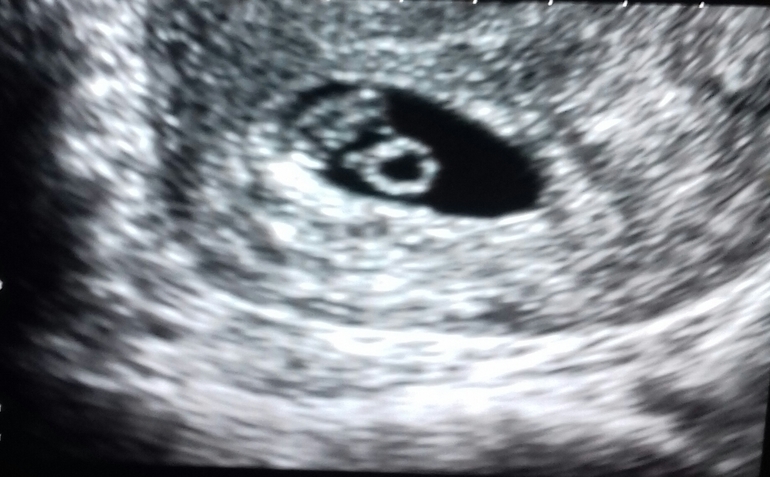

7 недель (32 дпп)

Всё о нашей беременностиСегодня было наше второе УЗИ! 🙏

СБ+ ЧСС 134

СВД - 14 мм, КТР - 7 мм, ЖМ - 3,4 мм

И разрешили сфотографировать с экрана.

Наш малыш (круг это желточный мешок).